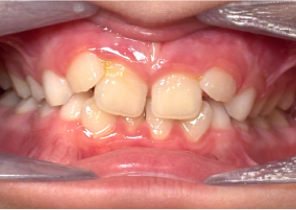

Case Report 2

7 years 11 months old, 24 stages of Invisalign® Palatal Expanders

Courtesy of Dr. David R. Boschken

Pre Invisalign Palatal Expander Expansion

Post Invisalign Palatal Expander Expansion

Post Invisalign Palatal Expander Treatment